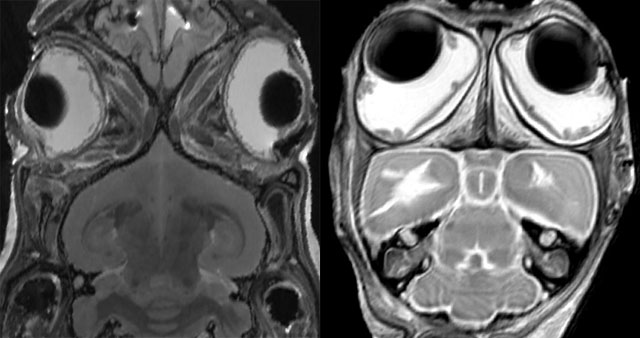

Non, répondent des chercheurs de l’université de Liverpool après avoir étudié, notamment par IRM, 51 espèces de mammifères (à gauche, un lapin, à droite, un chat). D’après leurs résultats, le cerveau des mammifères peut faire face à toutes les sollicitations survenant lors de la course, quel que soit l’endroit où sont placés les yeux : devant, latéralement ou même à l’arrière.

Source : Journal of Anatomy, février 2010, DOI 10.1111/j.1469-7580.2010.01211.x